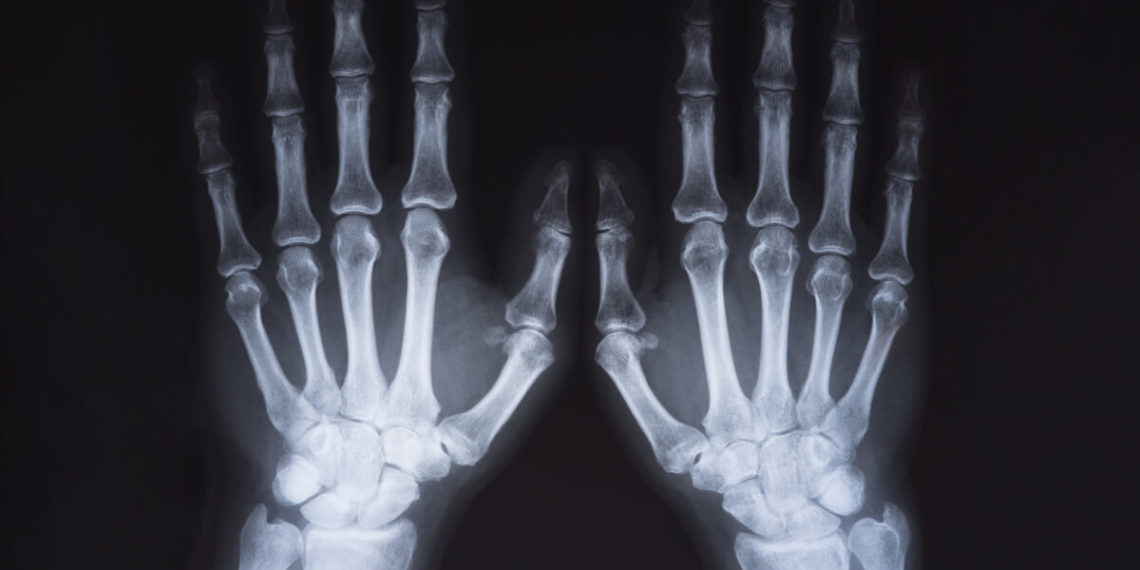

– osteofity

– chondrofity

– zwężenie szpary stawowej (zmiany ankylotyczne – zesztywnienie stawu)

– guzki Heberdena (DIP)

– guzki Boucharda (PIP)